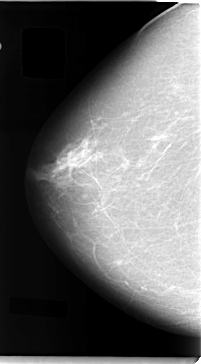

C_0040_1.RIGHT_MLO

RIGHT_CC LINES 4728 PIXELS_PER_LINE 2608 BITS_PER_PIXEL 12 RESOLUTION 50 NON_OVERLAY